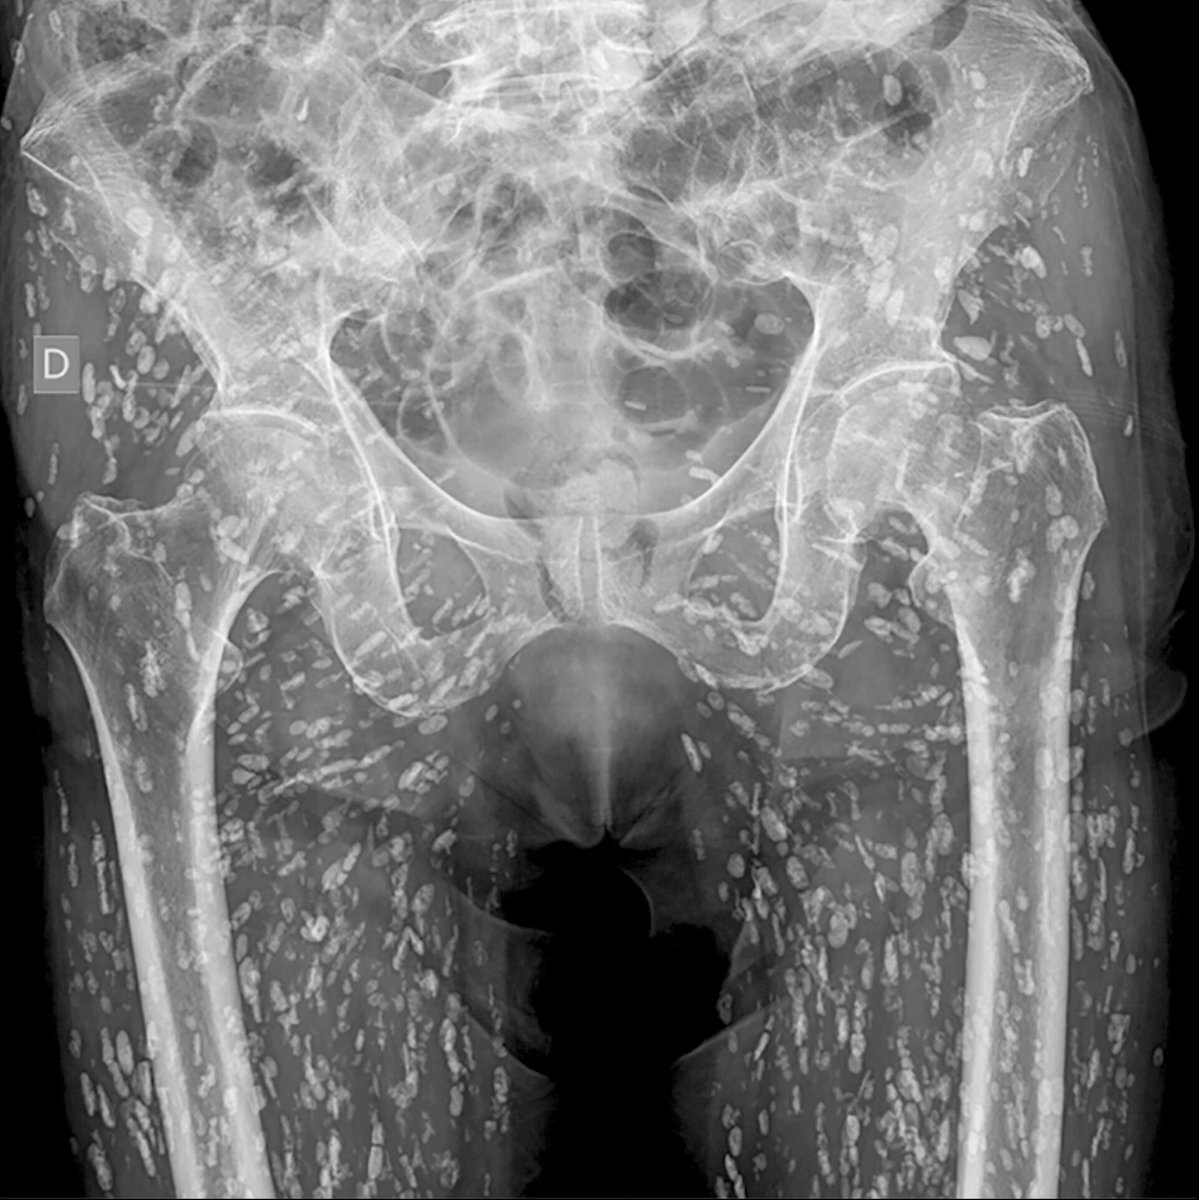

怖い😱 未加熱もしくは加熱不十分な豚肉を食べた事で有鉤条虫(Taenia solium/pork tapeworm)に感染し、腸管から筋肉中に移行し嚢虫症になっているレントゲン写真。股関節痛を主訴に撮影され付随的に発見されたもの。筋肉にあるだけなら命の危険はないけど、脳に移行すれば最悪死に至ることも。 x.com/em_resus/statu…

It's one of the most insane X-Rays I've ever seen. Here's a video I made breaking it down. Tell all your friends about this x.com/Blosept1/statu…